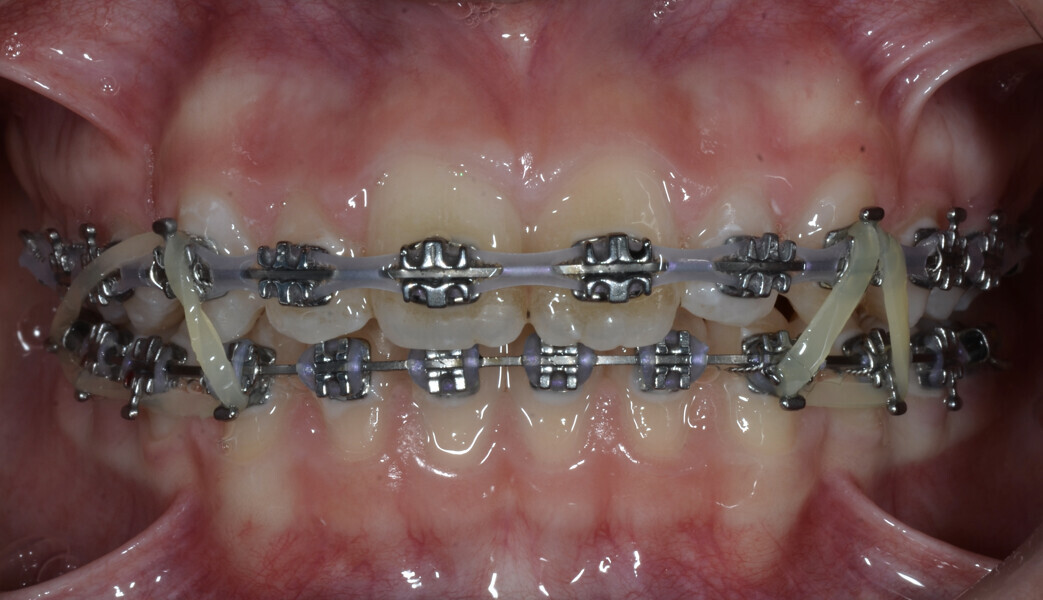

Fig. 1: Finishing the treatment with fixed orthodontic appliances.

The patient had undergone orthodontic treatment with fixed orthodontic appliances at the age of 11.5. She initially presented with a Class I relationship on the left side, a slight Class II tendency on the right side and moderate crowding in both arches, which was corrected with fixed orthodontic appliances at that stage (Figs. 1–11).